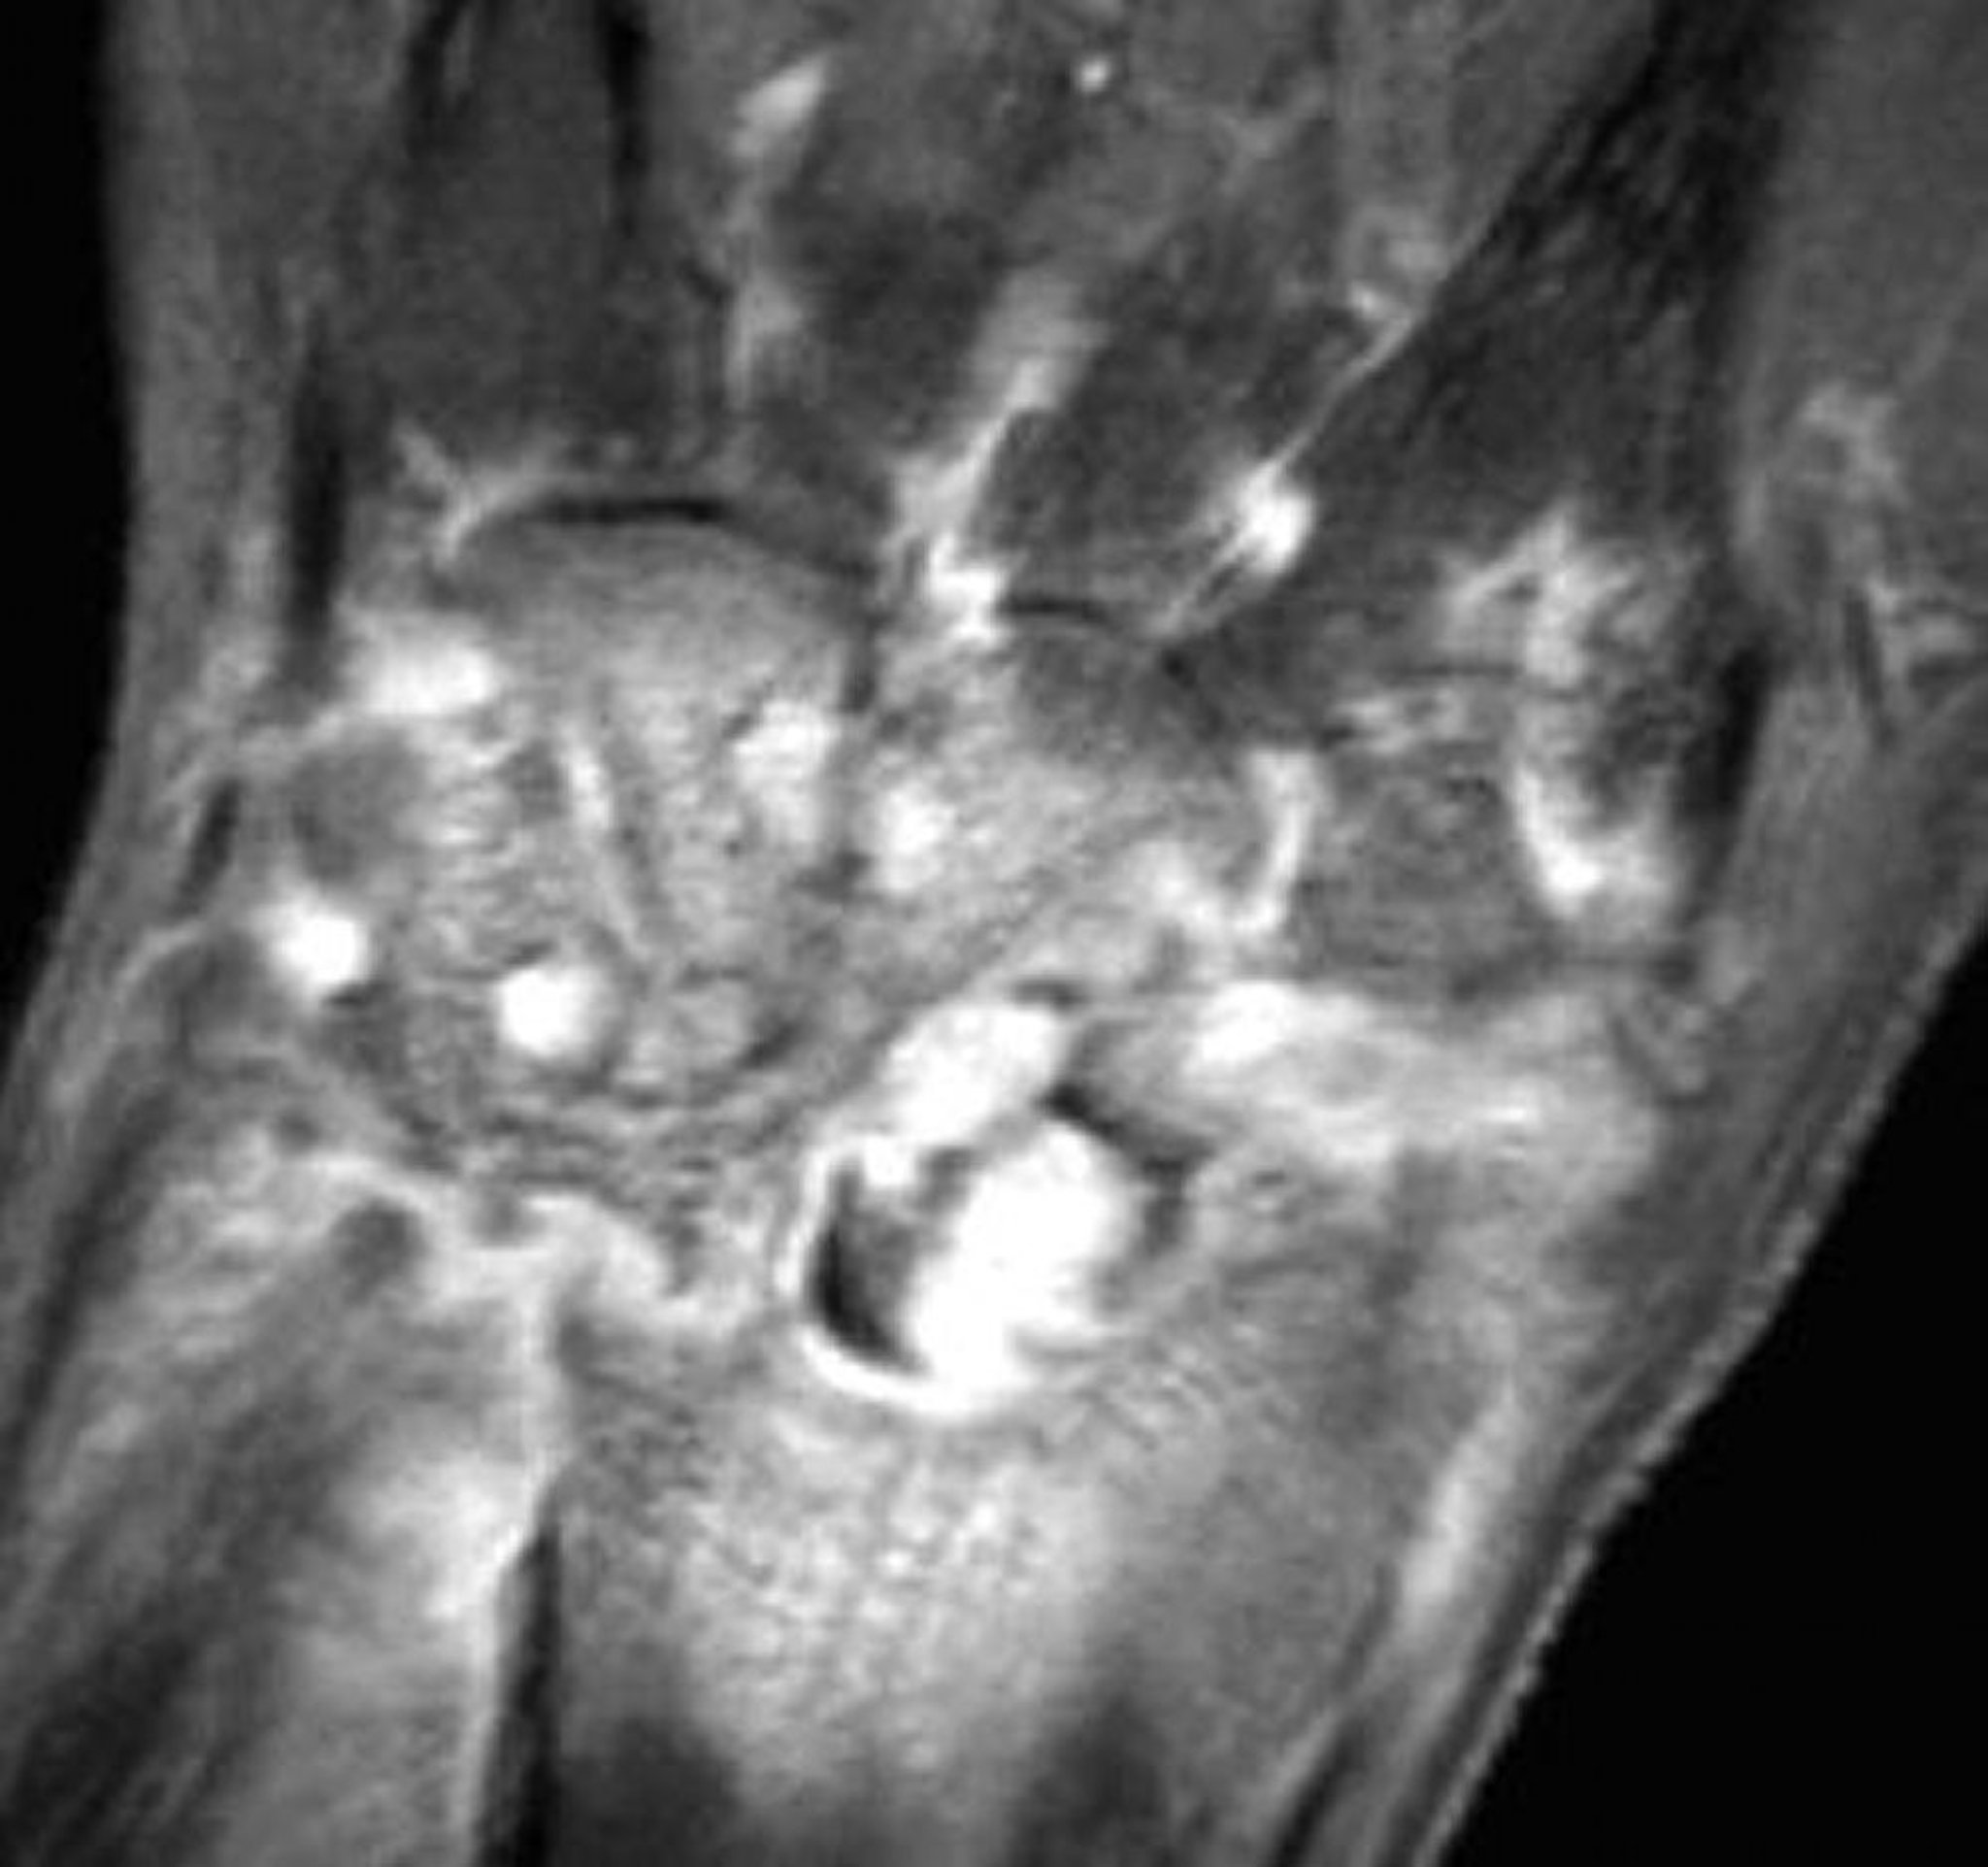

診察や穿刺吸引を行おうとしても容易に到達できない関節の場合(例,体軸関節),MRIを考慮する。MRIまたは超音波検査によって,関節液貯留または膿瘍がある部位を同定でき,診断および治療の両方を目的とした吸引または排出が可能となる(12)。MRIは,関連する骨髄炎を早い時期に示唆することがある(13)。テクネチウム99mを用いる骨シンチグラフィーは,感染性関節炎では偽陰性を示すことがある。さらに,炎症を起こした滑膜および代謝活性の高い骨で,増大した血流に伴う取り込みの増加を示すので,痛風のような非感染性の炎症性関節疾患で偽陽性を示すことがある。核医学検査およびMRIでは,感染症と結晶誘発性関節炎は鑑別されない(11)。